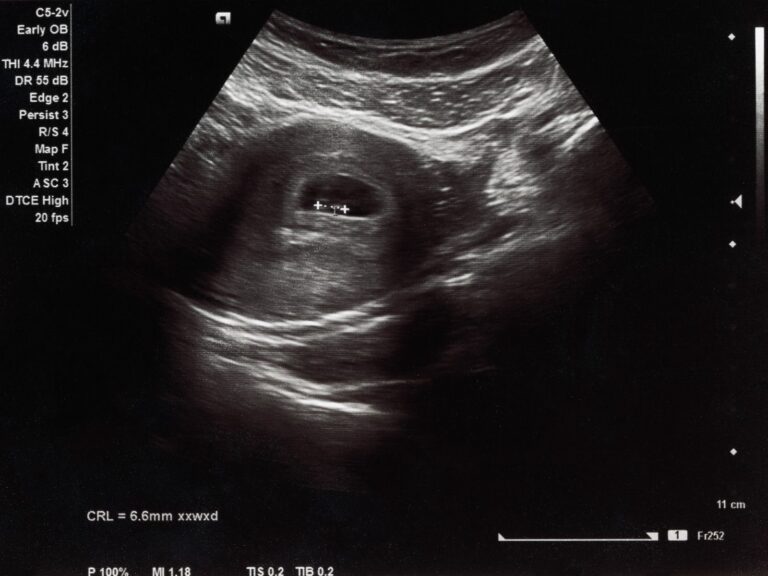

Every year, 73 million women worldwide have an abortion. I was one of them in 2023. As I went through my own abortion, the women around me started sharing their stories. These women were family members, friends, acquaintances, and even strangers – women from different generations and nationalities. I learned that my feelings of loneliness and shame were not unique to me, but were tied to a long lineage of women who have claimed the right to autonomy over their own bodies and lives.

In this project, “In the softness of the belly…”, I explore the interconnected care networks among women by meeting and conversing with over twenty women who underwent abortions, including my mother and both my grandmothers. Their stories and perspectives acted as a guide for a photographic diary, exploring different aspects of their experiences intertwined with my own. Through this intimate, highly personal photographic approach, which is primarily anchored in the mundane, I use analog snapshots and portraits to create a visual representation of what abortion can feel and look like.